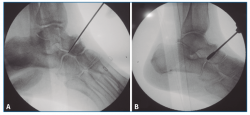

En primer lugar, se aborda la articulación TN como indican Carranza et al.(29); para ello, se marca en la piel el paquete neurovascular dorsal, se chequea la articulación por control fluoroscópico con una aguja intramuscular colocada entre el tendón tibial anterior (TA) y el extensor largo (EHL). Se realiza una incisión solo cutánea de 1 cm sobre la línea articular como el portal artroscópico dorsomedial descrito por Lui(24). Para evitar lesionar la arteria pedia o el nervio peroneal profundo, se realiza disección roma y penetración de la articulación astrágalo-escafoidea lo más cerca posible del TA. Finalmente, se cruenta la articulación bajo control fluoroscópico hasta tejido subcondral con escoplos y brocas motorizadas (Figura 1).

En segundo lugar, se aborda la articulación ST como indican Carranza et al.(30), se penetra la ST anterior y media por una incisión solo cutánea de 1 cm sobre el seno del tarso y la ST posterior por un portal posterolateral justo lateral al tendón de Aquiles, similar al portal artroscópico posterolateral descrito por van Dijk(31). Por estos 2 portales, finalmente se cruenta la articulación bajo control fluoroscópico hasta tejido subcondral con escoplos y brocas motorizadas (Figura 2).

Figura 1. Cruentación de la articulación astrágalo-escafoidea, bajo control fluoroscópico, hasta tejido subcondral, con escoplos (A) y brocas motorizadas (B).

Figura 2. Cruentación de la articulación subastragalina, bajo control fluoroscópico, hasta tejido subcondral, con escoplos (A) y brocas motorizadas (B y C).